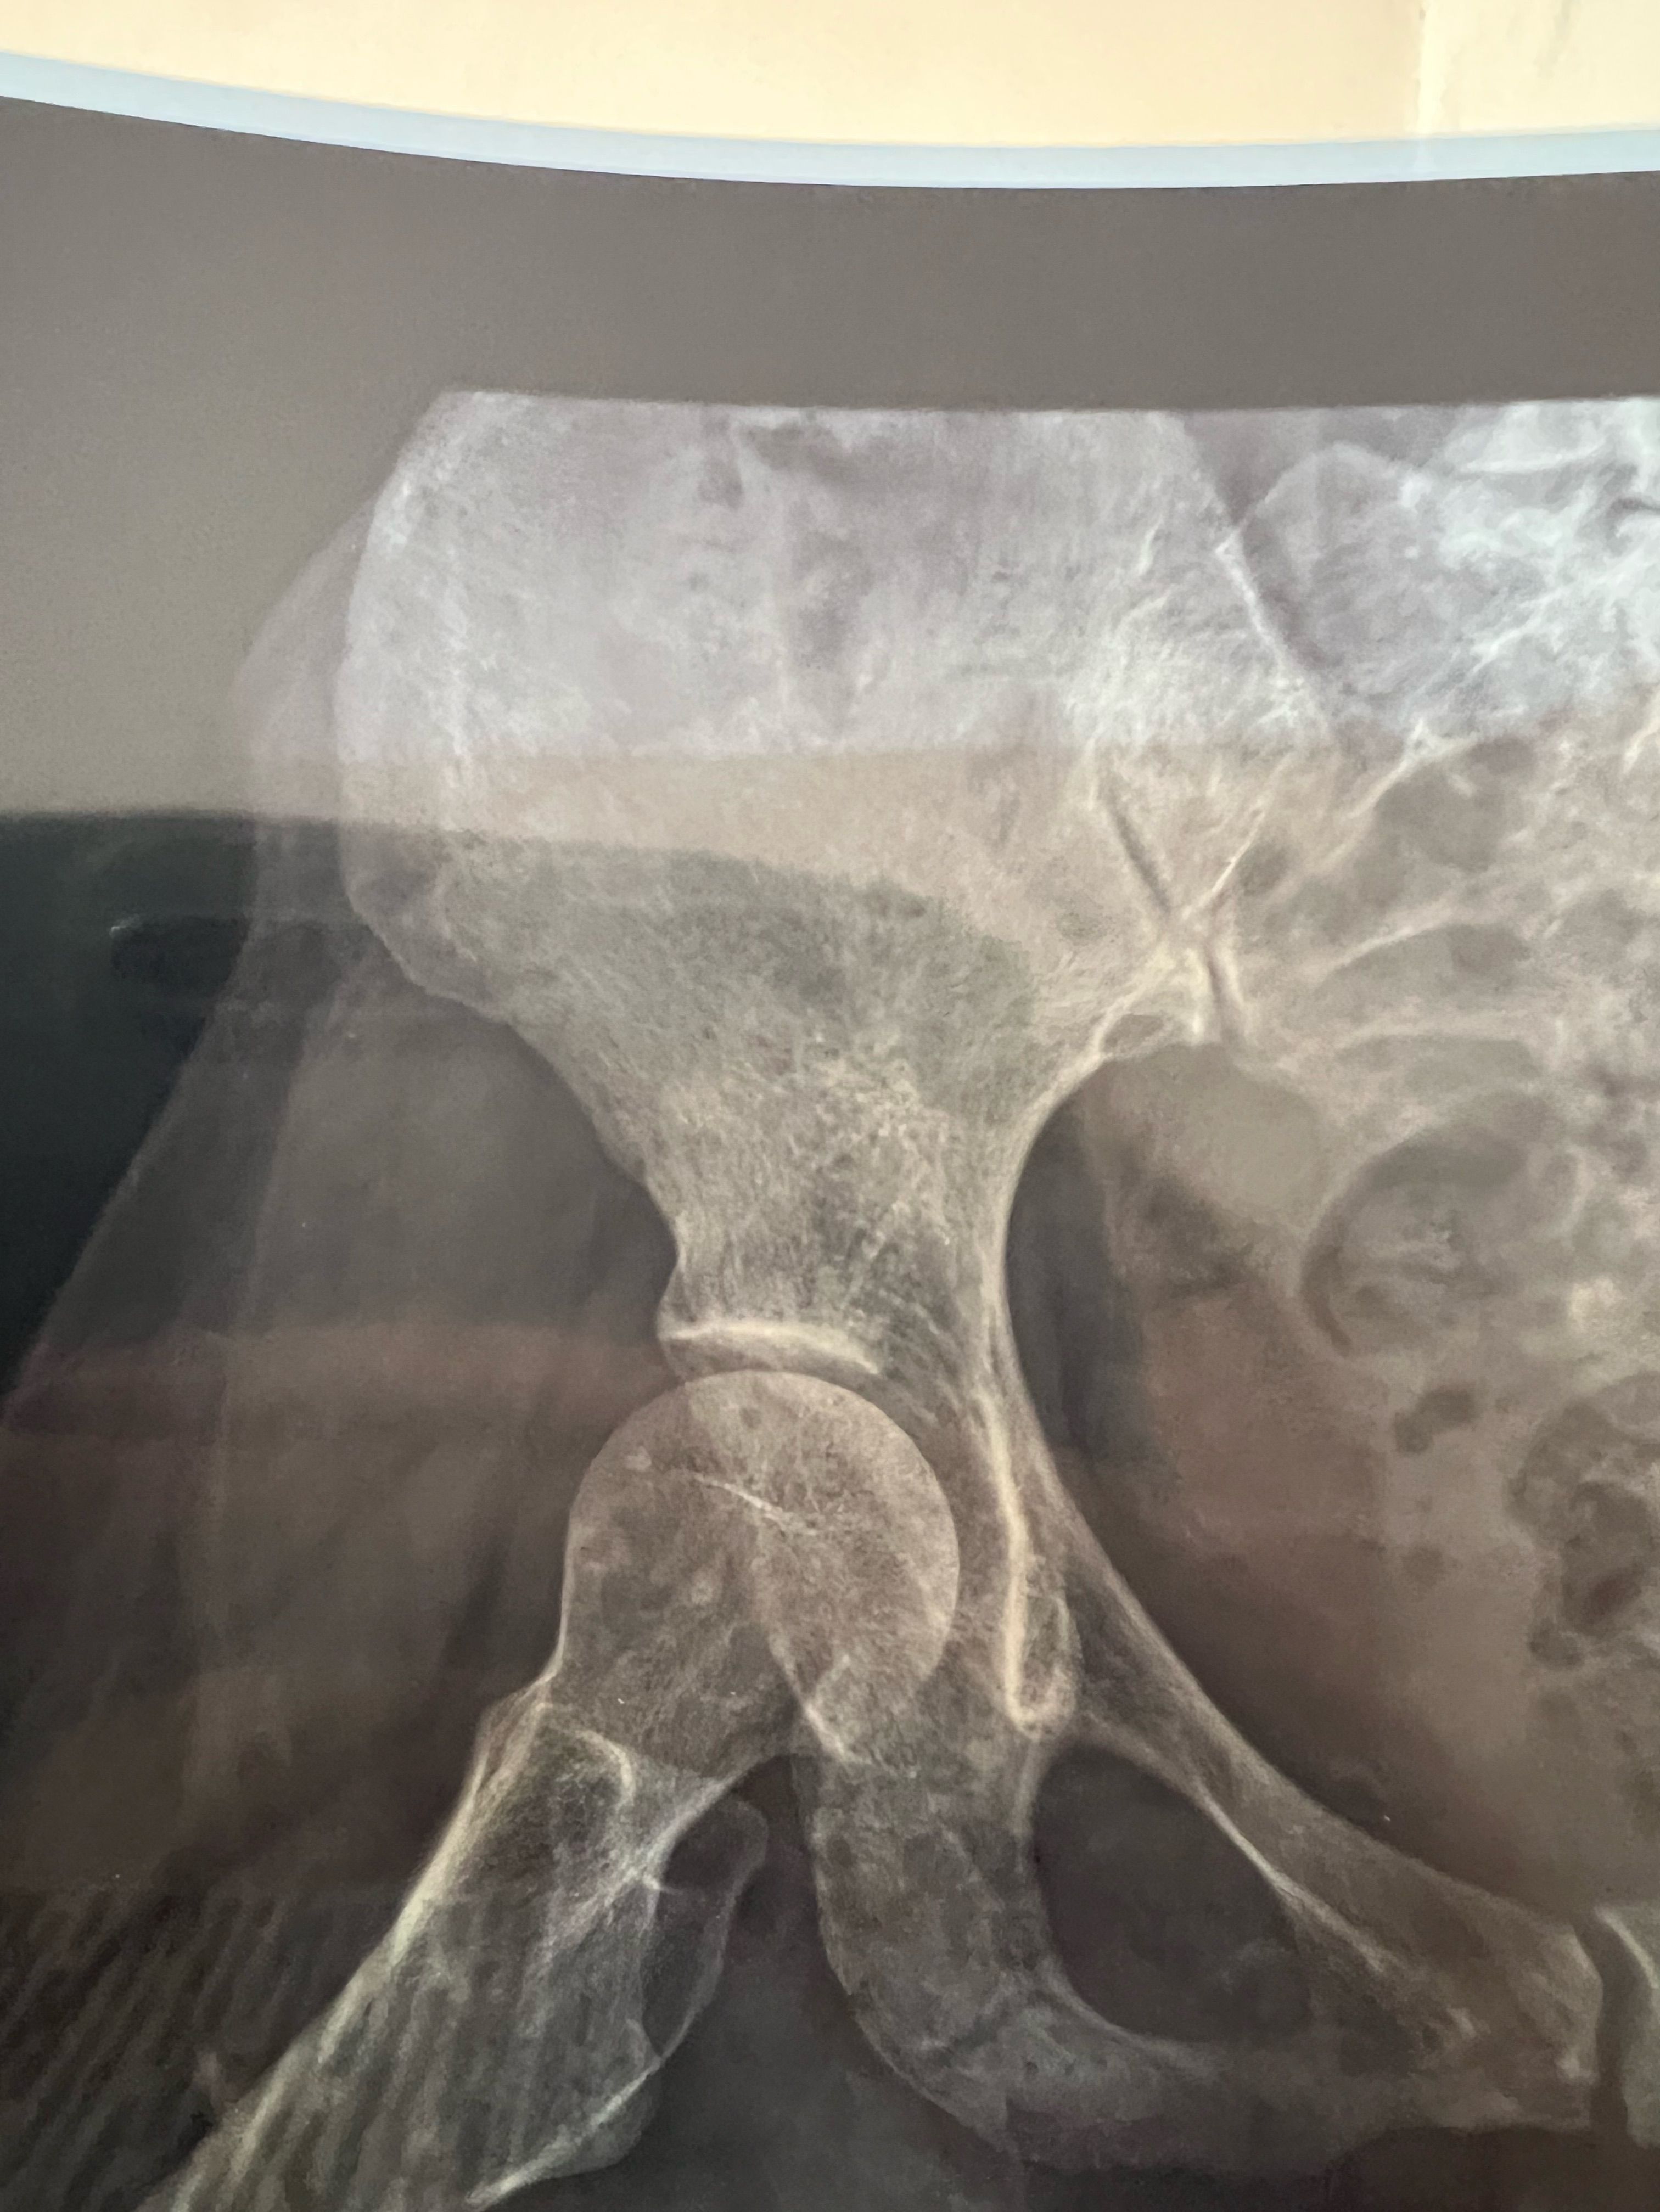

35 years old female

she falling down from high place please for diagnosis

Bone

Fracture